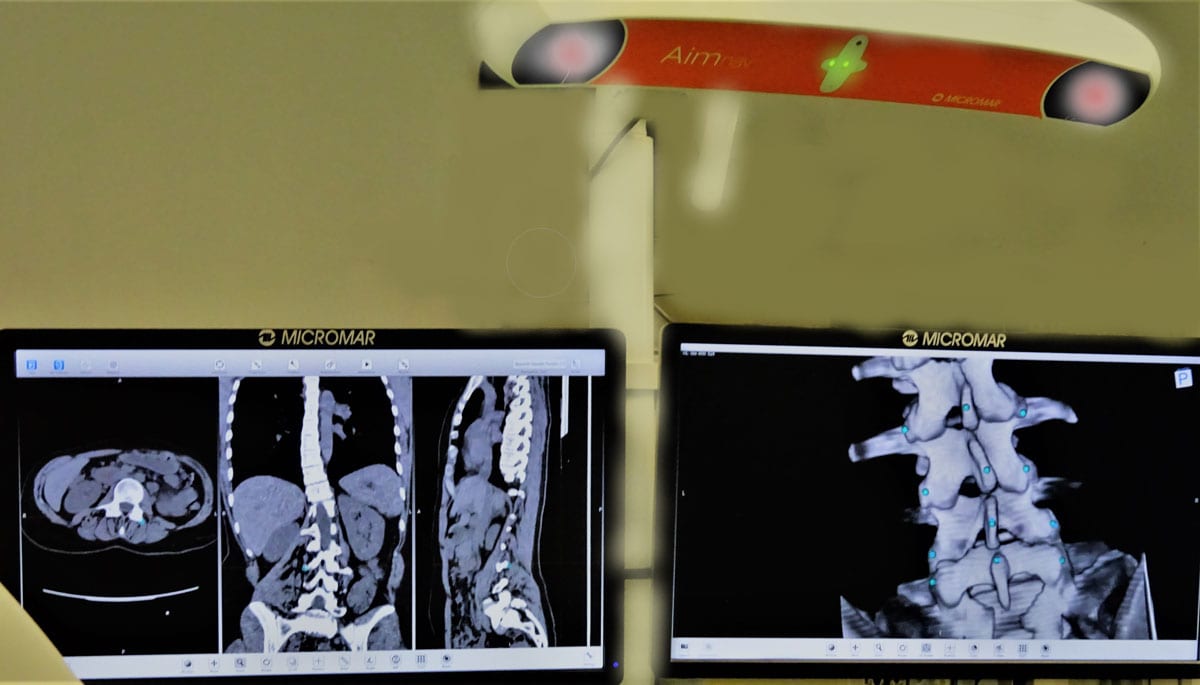

Η πλευρεγκαρσιεκτομή είναι μια εναλλακτική τεχνική προσέγγισης της θωρακικής μοίρας της σπονδυλικής στήλης, η οποία είναι ιδιαίτερα ωφέλιμη σε ασθενείς που έχουν διαγνωσθεί με όγκους στη σπονδυλική στήλη, οστεομυελίτιδα ή σοβαρά τραύματα που εντοπίζονται στα ανώτερα θωρακικά επίπεδα. Η πλευρεγκαρσιεκτομή συνήθως πραγματοποιείται σε ασθενείς που πάσχουν από έντονο πόνο στην πλάτη λόγω συμπίεσης των νωτιαίων νεύρων. Η συμπίεση αυτή μπορεί να προέρχεται λόγω ύπαρξης όγκου στα οστά ή στο νωτιαίο μυελό ή λόγω εκφυλιστικής νόσου της σπονδυλικής στήλης.

Η πλευρεγκαρσιεκτομή χαρακτηρίζεται από πολυάριθμα πλεονεκτήματα. Τα κυριότερα από αυτά είναι :